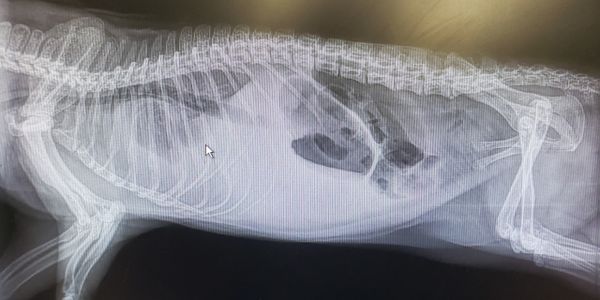

While holding him to trim just a few long nails he seemed to stress more than normal including stressed breathing.

He had not touched his cheese stick which was his favorite thing in the world. Kathi was on duty tending to the animals when Percy was able to be touched without running away and stood on top of his favorite shoe bed and was gasping for air with labored breathing. So off to the vet!

As we suspected Percy was in congestive heart failure. As severe as his condition was we decided that it was time to let him go. Before the vet even had a chance, in true Percy fashion, he took his own last breath without any assistance, he did it his way, in his own time, by his own will. He brought communities together and taught people across the nation about opossums. He will be greatly missed.